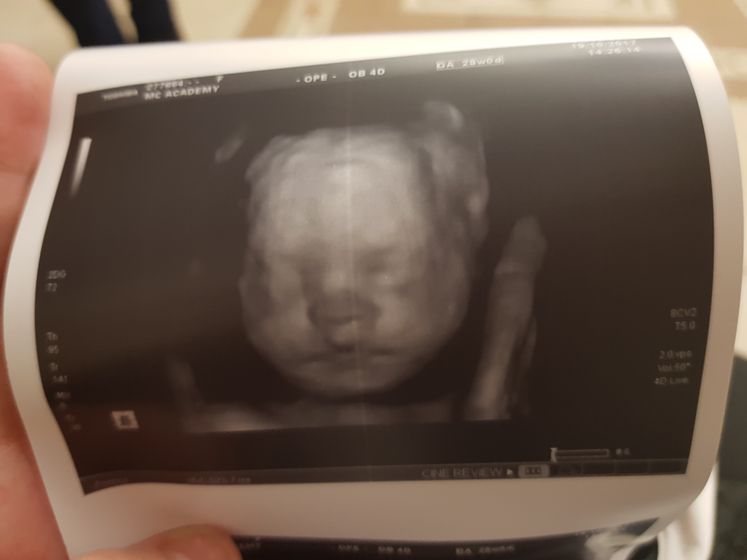

Сходила я сегодня на узи. Сидим на попке( все у нас в норме. Срок стоит 30-31 неделя, вот так вот) значит вдм соответствует узи)) весим мы 1418) и вот мы))

В академии, на стасово 18. Запись на флешку и фото на память) стоимость 1950

Так это 3д узи) оно на много качественее)